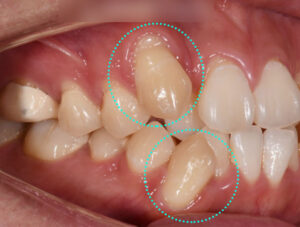

덧니 때문에 발생하는 문제는 어떤 것들이 있을까? 중랑구 양원역 치과 치아교정 증례

삐뚠 치열로 고민을 갖고 있는 분들 중 '덧니' 때문에 고민을 갖고 있는 경우가 정말 많은데요. 외적 콤플렉스 말고도 여러 문제들의 원인이 될 수 있습니다. ​ 환자의 진료 과정을 살펴보기 전,…